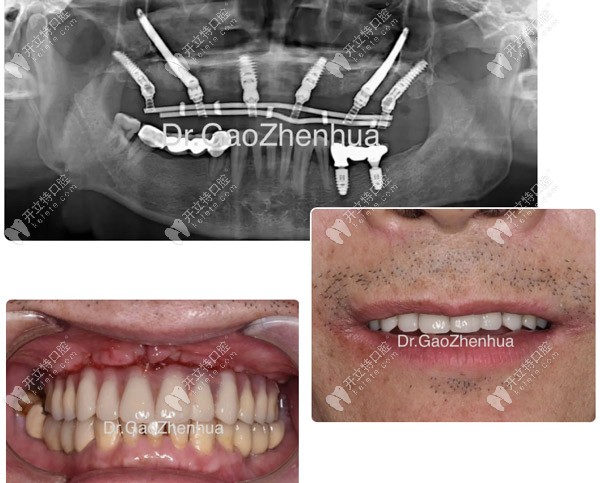

顴種植位點(diǎn)不得已還是放在貫通位點(diǎn),竇底適當(dāng)植骨,前牙區(qū)靠鼻底硬骨板雙皮質(zhì)固位獲得穩(wěn)定性,經(jīng)過2個(gè)小時(shí)的手術(shù),實(shí)現(xiàn)了即刻負(fù)重的預(yù)期!

當(dāng)天做完VIIV穿顴穿翼手術(shù)

當(dāng)天做完VIIV穿顴穿翼手術(shù)▲